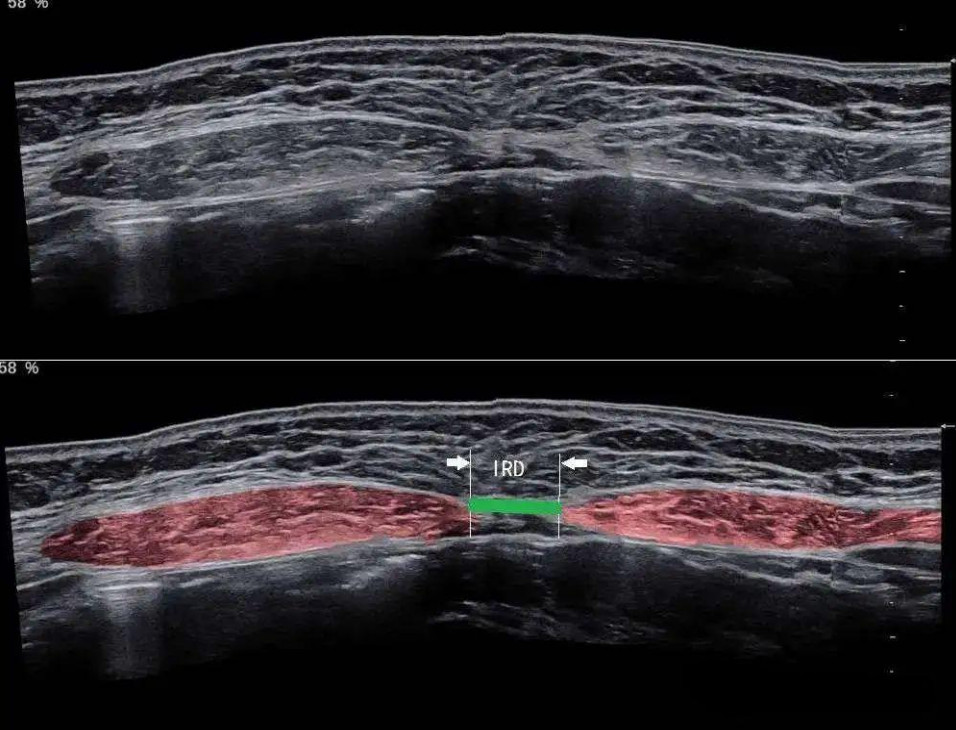

腹直肌分离是由于后天因素使腹直肌沿着肌肉长轴分离,腹白线被拉伸和变薄,使两侧原本平行并列的腹直肌从腹中线处向腹壁两侧分开,表现为腹直肌间距 (IRD) 超过正常宽度,且普遍合并腹壁肌肉松弛,但不合并筋膜缺损。

腹直肌分离是产后常见的身体结构改变。产后6~8周腹直肌仍然不能恢复到两指或者两指以内的称产后腹直肌分离。

目前,超声作为腹直肌分离检测和诊断的“金标准”已成为临床共识,是临床筛查产后腹直肌分离的首选方法。